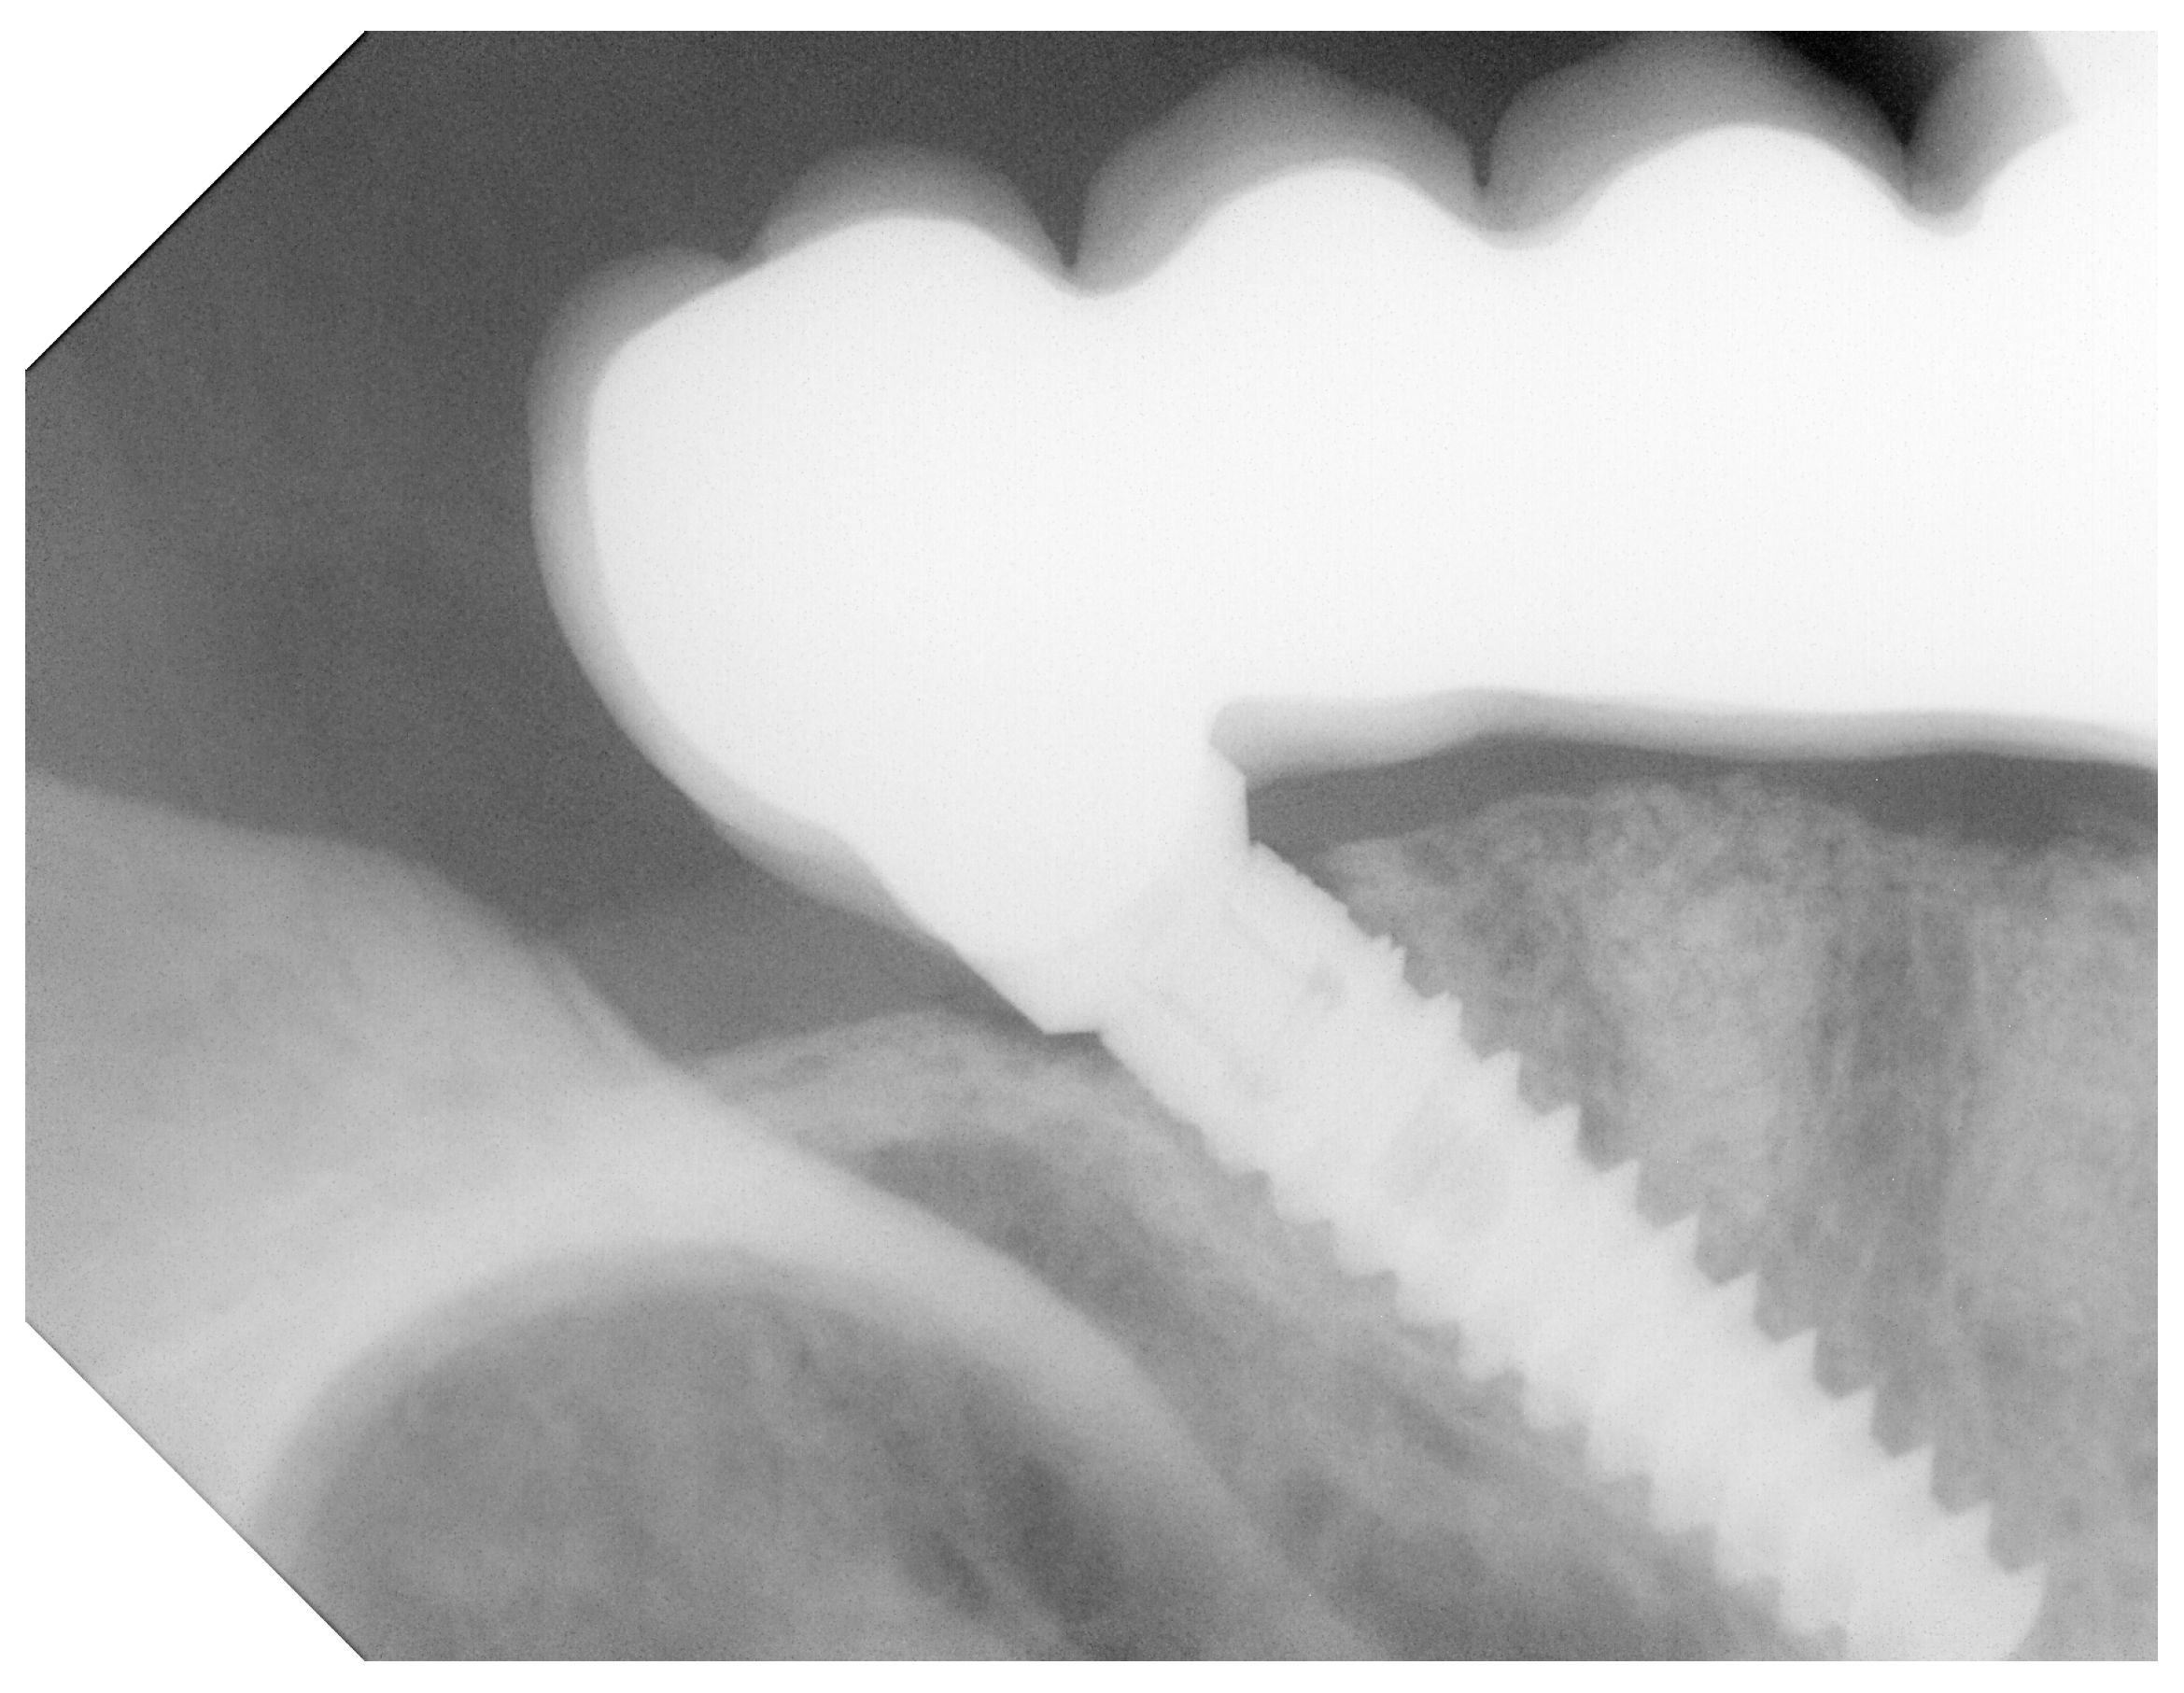

2.2. Preoperative Measurements

3.3. Bone Loss